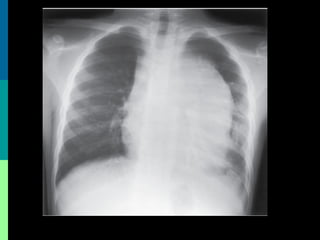

• #32 Coagulopathy, usually mild, can be seen in 3 to 5 percent of patients, most of whom have T cell ALL The level of serum lactate dehydrogenase is increased in most patients with ALL and is well correlated with the size of the leukemic infiltrate. 77 Increased levels of serum uric acid are common in patients with a large leukemic cell burden, a finding that reflects an increased rate of purine catabolism. Patients with massive renal involvement can have increased levels of creatinine, urea nitrogen, uric acid, and phosphorus. Occasionally, patients with T cell ALL present with acute renal failure, despite a relatively small leukemic infiltrate. 78 Rarely, patients present with hypercalcemia resulting from release of parathyroid hormone-like protein from lymphoblasts and leukemic infiltration of bone. 79 Liver dysfunction as a result of leukemic infiltration occurs in 10 to 20 percent of patients, usually is mild, and has no important clinical or prognostic consequences. 59 Serum immunoglobulin levels (mostly IgA and IgM classes) are modestly decreased in approximately one third of children with ALL. The reduction reflects the decreased number and impaired function of normal lymphocytes. 80 Urinalysis may show microscopic hematuria and the presence of uric acid crystals. Chest radiography: Evaluate for a mediastinal mass. In general, no other imaging studies are required. However, if the physical examination reveals enlarged testes, perform ultrasonography to evaluate for testicular infiltration. Testicular ultrasonography: Perform testicular ultrasonography if the testes are enlarged on physical examination. Renal ultrasonography: Some clinicians prefer to evaluate for leukemic kidney involvement to assess the risk of tumor lysis syndrome. Echocardiography and ECG: Obtain an echocardiogram and an ECG before anthracyclines are administered. potassium, phosphorus

• #33 Chest radiography is needed to detect enlargement of the thymus or mediastinal nodes, with or without pleural effusion (see Fig. 91-3). Although bony abnormalities, such as metaphyseal banding, periosteal reactions, osteolysis, osteosclerosis, and osteopenia, can be found in 50 percent of patients, especially children with low leukocyte counts at presentation, 81 skeletal roentgenography is not necessary for case management. Spinal roentgenography is useful in patients with suspected vertebral collapse.